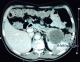

Mr M.D âgé de 51 ans sans antécédents pathologiques hospitalisé pour douleurs épigastrique associées à des vomissements évoluant depuis 6 mois qui s'étaient accentuées la veille de son admission. L'examen avait trouvé un patient avec un état général conservé subfébrile à 37,9° présentant une sensibilité épigastrique et de l'hypochondre droit à la palpation de l'abdomen, mais sans masse palpable. Il n'y avait pas d'ictère. La biologie avait noté, une amylasémie a 10 fois la normale et une hyperleucocytose à 21000el/mm3. Les bilans hépatique et rénal étaient sans anomalies. Une échographie abdominale réalisée en urgence avait mis en évidence un pancréas augmenté de taille avec une formation kystique de la queue du pancréas de 54 mm. La vésicule était alithiasique. Il n'y avait pas de dilatation des voies biliaires (Figure 1). La tomodensitométrie avait objectivé un pancréas atrophique, siège au niveau de sa portion caudale d'une formation kystique de 6 cm uniloculaire adhérant intimement à la rate. Il existait une dilatation modérée du canal de Wirsung mais sans dilatation de la voie biliaire principale (Figure 2, Figure 3).

Figure 2: TDM coupe transversale: formation kystique de 6 cm uniloculaire de la queue du pancréas adhérant intimement à la rate avec dilatation modérée du canal de Wirsung

Figure 3: TDM coupe longitudinale montrant la lésion kystique uniloculaire